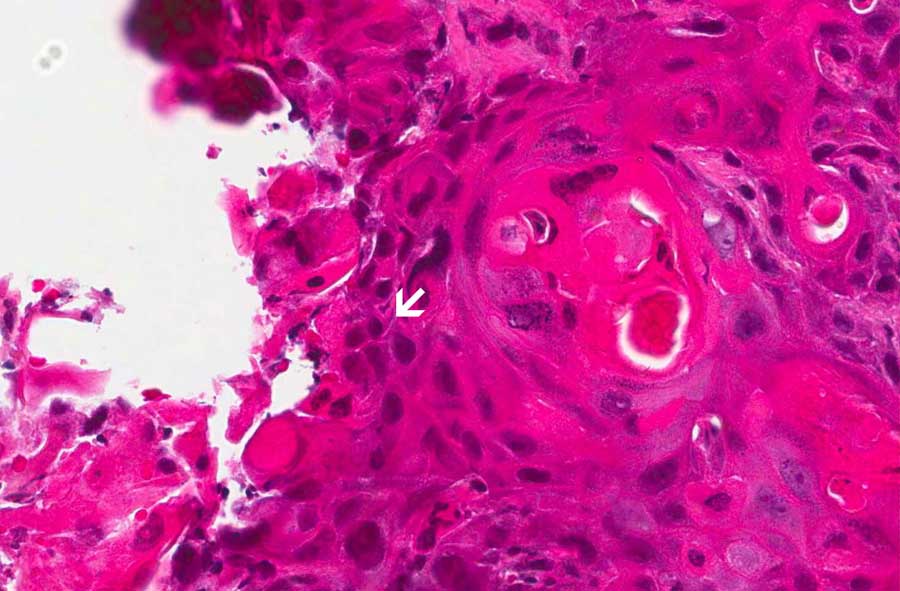

1: Note the keratinizing pearls (arrow in the low-magnification

image) and the intecellular bridges (arrow in the high-magnification

image. |

The salient features are the keratin pearls (area 1) which is a

diagnostic feature of squamous cell carcinoma. Intercellular bridges

are also present which is also a classic feature of squmous cell

carcinoma.